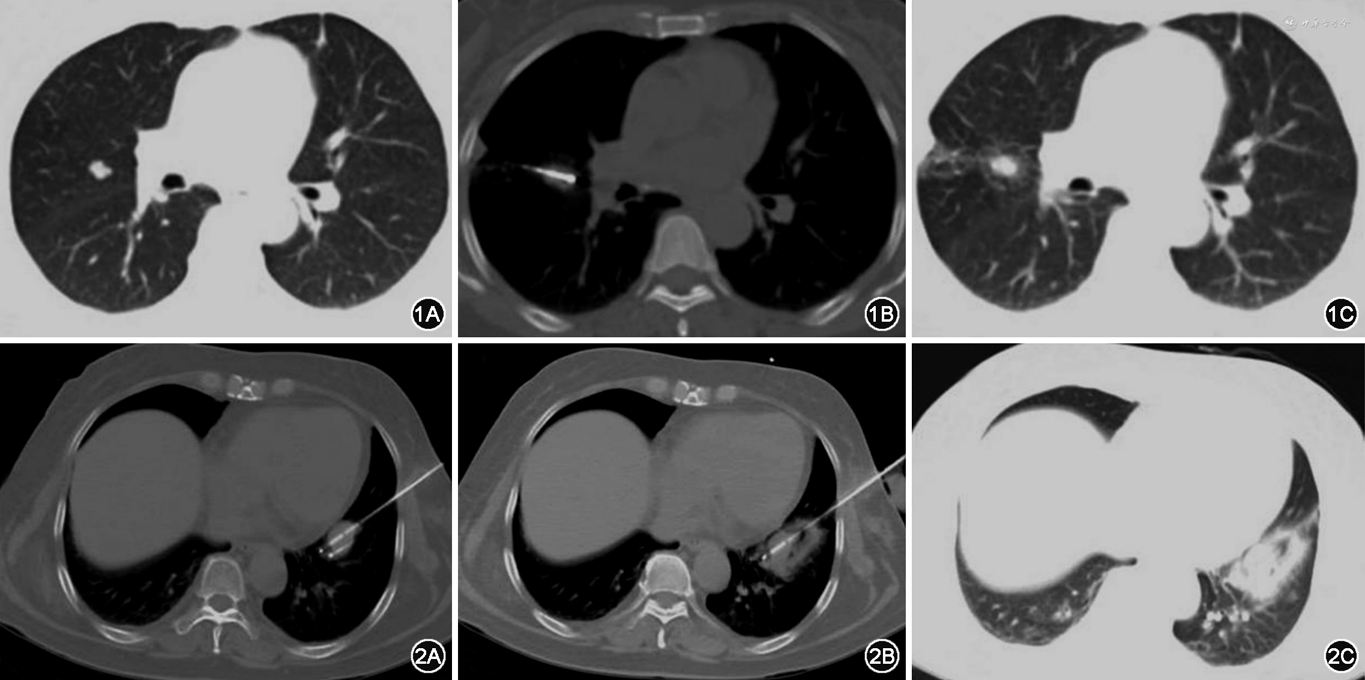

1.RFA:根据肿瘤大小选择裸露端2 cm或者3 cm的射频电极针,按设计进针计划在CT引导下穿刺至理想位置,开启射频系统,选择阻抗模式,进行消融。消融终点为肿瘤病灶周围出现晕征或根据射频消融针说明书消融范围超过靶病变边缘5~10 mm。术后即刻行CT扫描,确定有无并发症(图1)。

2.CYA:依据病灶大小及形态,准备相应数量的冷冻探针(17G,直径1.47 mm)在CT引导下将冷冻探针穿刺至计划位置。将装有温水的无菌手套置于皮肤冷冻探针周围保护皮肤,采用适当压力冷冻15 min、复温3 min作为一治疗循环,共治疗2个循环。术中每5~10 min 进行一次CT扫描,监测冰球大小,判定消融范围(理想消融范围为冰球超过靶病变0.5~1 cm),术后即刻行CT平扫确定有无并发症(图2)。